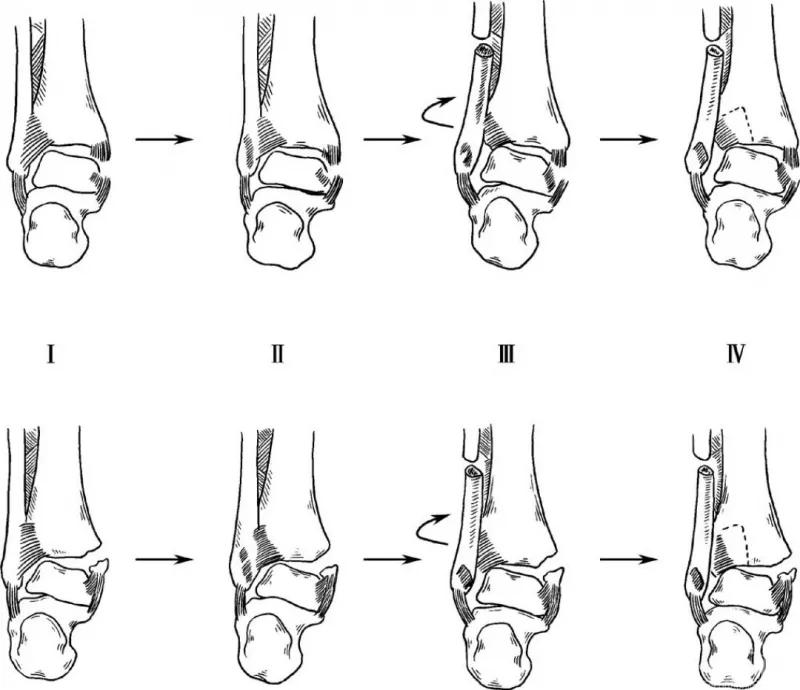

2. 旋后—外旋型

当患足处在旋后位时,此时如受外力迫使躯体内旋,患足相对外旋下胫腓前联合韧带拉紧导致下胫腓前联合断裂,或前外结节撕脱骨折,后者更常见。韧带断裂或在止点撕脱,外力持续则腓骨发生螺旋形骨折。骨折线从前下至后上。

外力继续可使下胫腓后联合断裂,或后外结节撕脱骨折,有些病例距骨的外力可能直接作用到内踝而不发生后侧损伤。如外力很大最后内侧结构受累,三角韧带断裂或内踝骨折,距骨向外移位。

如果骨折在腓骨前结节以下,下胫腓前联合仍然完整。通常骨折在前结节水平或恰在前结节上方,下胫腓联合韧带部分或全部断裂。罕有旋后外旋骨折,腓骨骨折线在下胫腓联合韧带以上水平,伴有骨间膜和联合韧带损伤。旋后—外旋型骨折分四度(图2)。

图2 旋后—外旋型

4. 旋前—外旋型

踝内侧首先损伤,继而下胫腓前联合韧带断裂或前结节撕脱骨折,随后腓骨骨折,骨折线位于胫腓联合上方。腓骨骨折线斜形,但从前上到后下。骨间韧带损伤。外力如继续可造成下胫腓后联合断裂,或胫骨后外侧撕脱骨折。

由于外旋也可能造成腓骨近端骨折。旋前-外旋型骨折分四度(图4)。Maisonneuve骨折是特殊的高位腓骨骨折,下胫腓分离,伴内踝骨折或三角韧带损伤。需固定下胫腓联合,也容易漏诊。

图4 旋前—外旋型